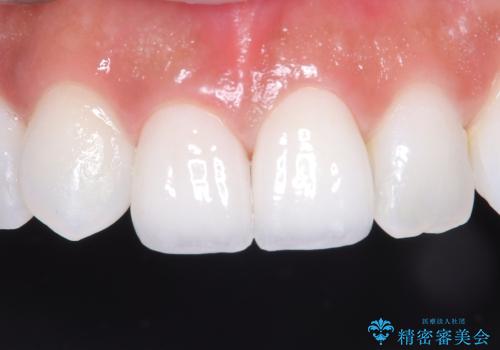

かかりつけ医にて応急的に修復してますが根本的な治療を希望され、矯正的挺出を行ったのち、歯周外科を行い、歯冠修復をしております。

歯肉縁下の水平破折をきちんと治療するためには時間も費用もかかります。